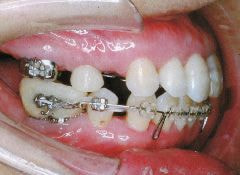

治療例2 (補綴処置+矯正)